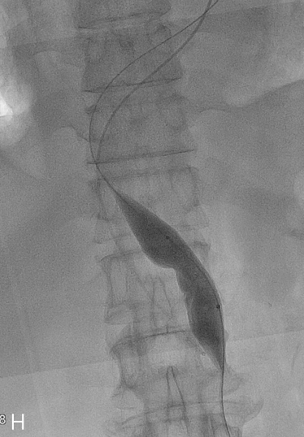

Fig 2H

(H) After puncture, serial balloon dilatation was performed upto 25mm in diameter.